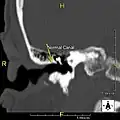

-

Normal ear canal -

Exostosis in ear canal -

Exostosis in ear canal

The normal ear canal is approximately 7 mm in diameter and has a volume of approximately 0.8 ml (approximately one-sixth of a teaspoon).[5] As the condition progresses, the diameter narrows and can even close completely if untreated, although people generally seek help once the passage has constricted to 0.5–2 mm due to the noticeable hearing impairment. While not necessarily harmful in and of itself, constriction of the ear canal from these growths can trap debris, leading to painful and difficult to treat infections.